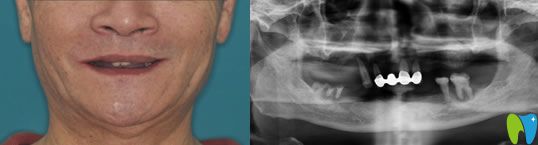

【全口種植牙前后對(duì)比圖】

種植牙前:全口牙缺失;

種植牙后顧客評(píng)價(jià):自己在智媄口腔做的全口種植牙吃東西和真牙一樣,已經(jīng)幾年了,但是醫(yī)護(hù)人員每年都會(huì)提醒過(guò)來(lái)復(fù)查,服務(wù)和技術(shù)都很好!